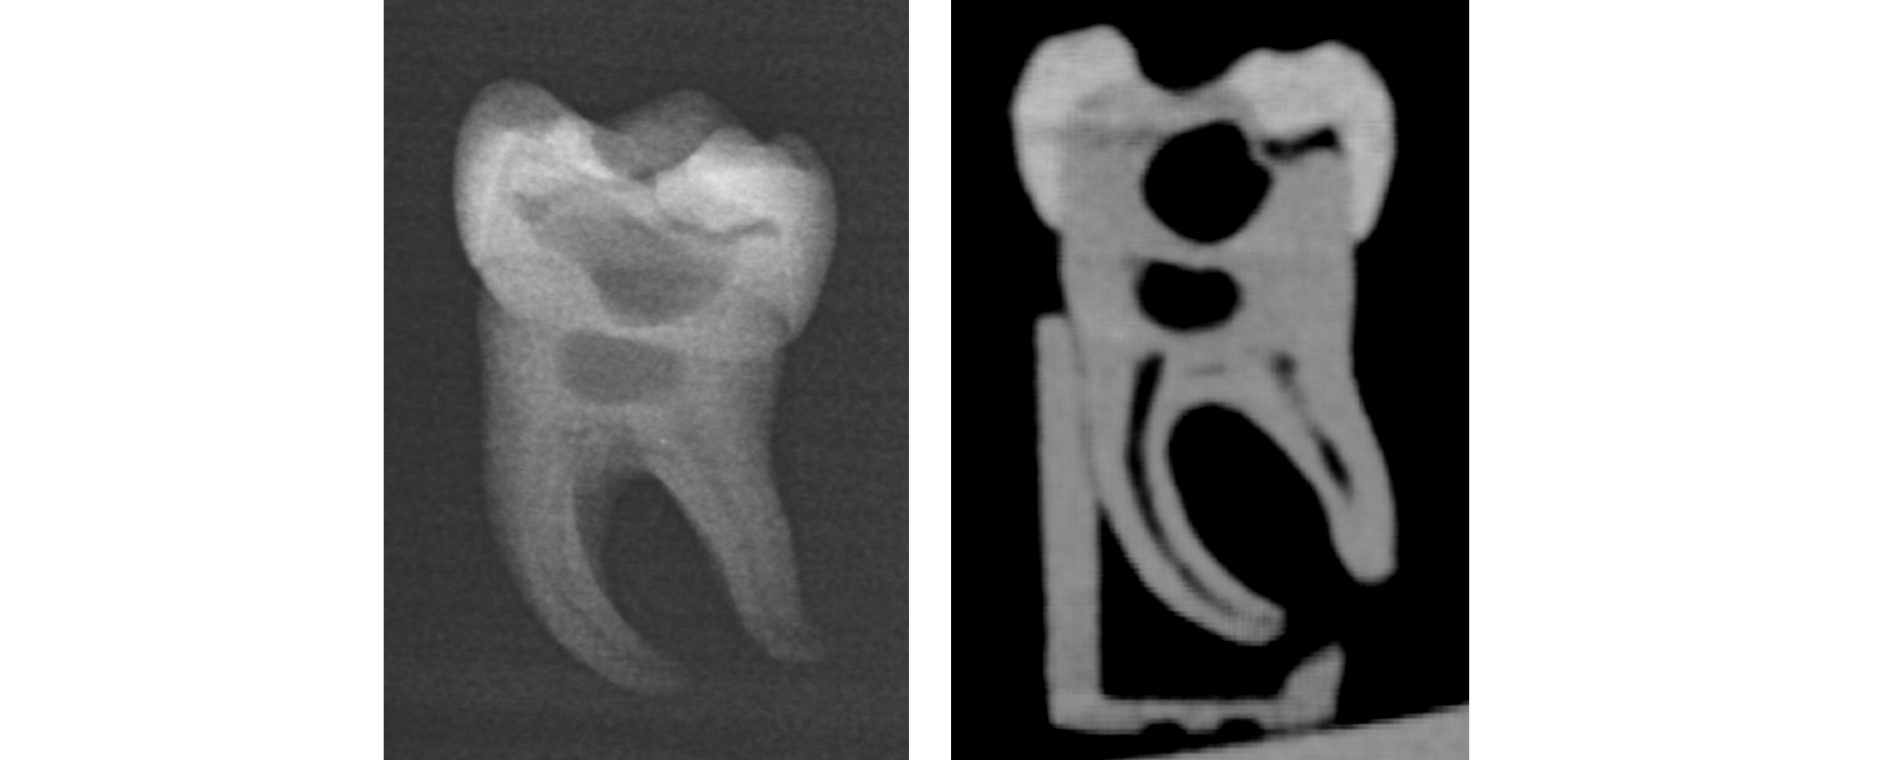

Studien belegen den hohen Lerneffekt, die Akzeptanz bei Studierenden und den didaktischen Nutzen des universellen Übungszahns bei einer Kariesexkavation und beim Präparieren von Klebebrücken belegten bereits Studien im Journal BMC Medical Education und in Scientific Reports. Jetzt wurde die Erprobung des 3D-gedruckten Zahns bei der Wurzelkanalbehandlung veröffentlicht.

38 Zahnmedizinstudierende bewerteten den 3D-gedruckten Zahn als eine signifikant bessere Übungsmöglichkeit als die üblichen transparenten Acrylblöcke, die oft zum Üben für Wurzelkanalbehandlungen zum Einsatz kommen, und fast ebenbürtig zu natürlichen Zähnen, insbesondere hinsichtlich Realismus, Handhabung und Lernwert. „Der gedruckte Zahn ist nicht nur realistisch und kosteneffizient, sondern auch fair. Mit dem neuen Übungszahn haben wir für alle Studierenden identische Prüfungs- und Lernbedingungen geschaffen“, resümiert Erstautorin Isabella Di Lorenzo.

Auch Oberarzt Dr. Michael del Hougne M.Sc., Kursleiter im Bereich der klinischen Lehre, ist vom neuen Übungszahn begeistert. „Unsere Studierenden können an dem Modell sogar die elektrische Längenmessung des Wurzelkanals sehr realistisch üben. Dafür mussten wir jedoch etwas tricksen, um die benötigte Leitfähigkeit herzustellen, denn der Zahn ist aus Harz, das den Strom nicht leitet.“ Im nächsten Schritt sollen 3D-Zähne mit unterschiedlichen Wurzelkanalformen entwickelt werden, um die klinischen Herausforderungen, die sich aus der anatomischen Vielfalt ergeben, zu simulieren.